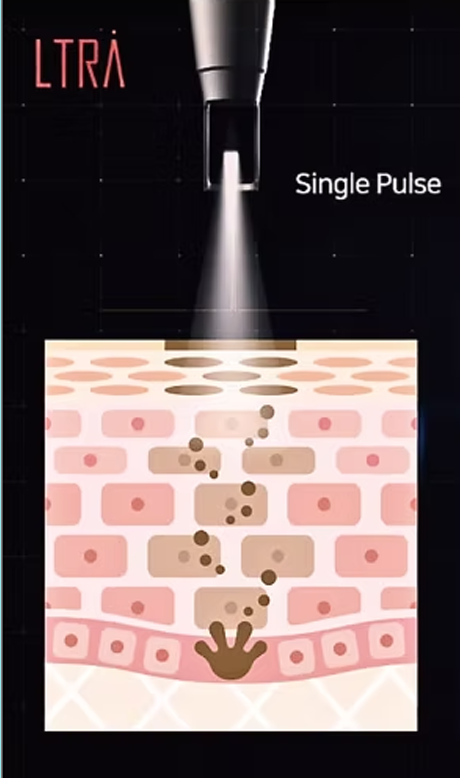

표피 손상없는

멀티펄스 레이저

최대출력 3,000mJ의 에너지에서 4~8개의 다중펄스를 발생시켜

강력하고 부드러운, 레이저 치료의 부작용을 최소화한 시술입니다.

LIOB(Laser Induced Optical Breakdown) 효과를 이용해

플라즈마를 발생시키고 이 효과로 손상된 조직을 회복시켜

매끄러운 피부로 거듭나게 합니다.